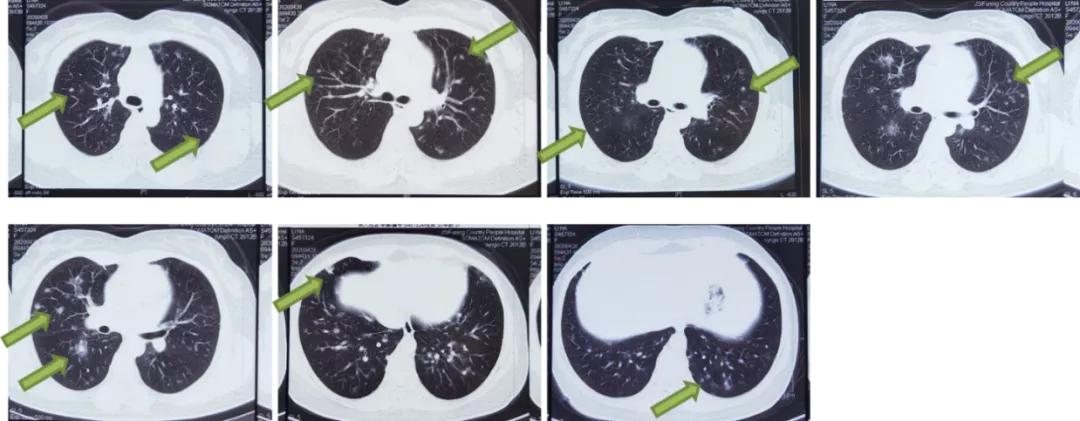

4月28日行胸部CT显示两肺多发结节(最大直径0.8cm),性质待定;纵隔小淋巴结,两肺局部少许炎症。

图2:胸部CT(2020.4.28)